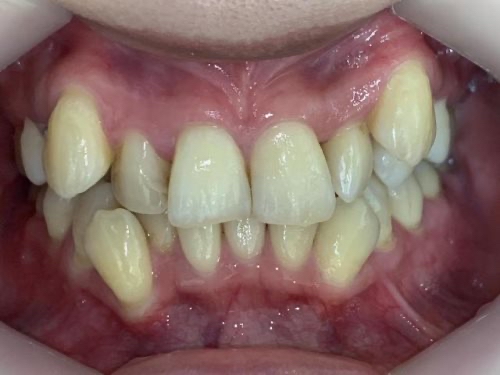

叢生(そうせい)

叢生(そうせい)とはいわゆるガタガタの歯並びのことを指します。

叢生の方は歯が複雑に生えて並んでいることから磨き残しやそれに伴う歯周病のリスクが通常よりも高い傾向にあります。実際に当院に歯並びの相談で来院される方にも歯の磨きずらさを感じている方が多くいらっしゃいます。

満員電車を想像してみてください。たくさんの人がいる窮屈な電車の中で、少しのスペースに不自然な体制で人が密集していますよね。歯並びも同じです。十分なスペースがない歯茎に無理やり歯が生えている状態、それが叢生です。